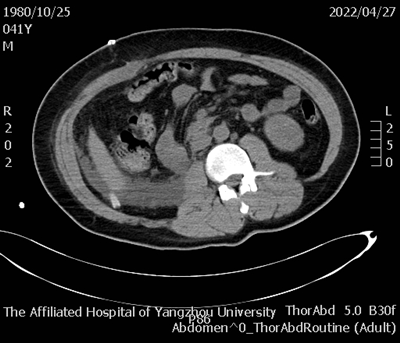

据悉,患者因“下腹部胀痛2天加重6小时”于西区医院外科急诊就医,经全腹部CT检查提示:右侧腹膜后巨大占位并破裂、出血,不除外肾脏或肾肿瘤破裂。据此情况,外科急诊遂收治泌尿外科进行救治。

王小祥表示,该患者右肾肿瘤的直径长达30cm实属罕见,对我院临床决策和手术技术提出了更高的要求和挑战。本次在我院多学科密切协助下患者得以术后快速康复,既是我院整体强大的急危重症处置能力的体现,也为我们今后处理类似病例提供了宝贵的经验。